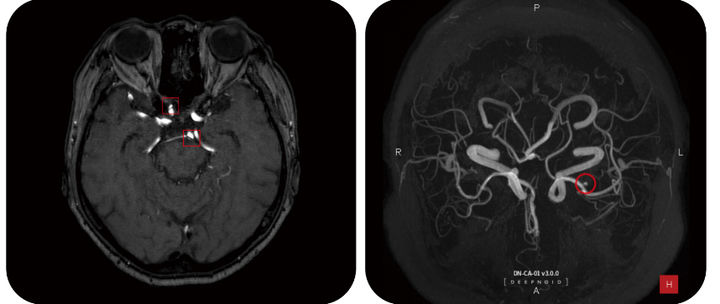

![[t서울=뉴시스] 딥노이드는 내달 5일부터 3일간 개최되는 일본 의료 산업 전시회 ‘메디컬 재팬 오사카 2025 (Medical Japan OSAKA2025)’에 부스 참여한다고 25일 밝혔다. 사진은 딥뉴로 판독 화면. (사진=딥뉴로 제공) 2025.02.25. photo@newsis.com *재판매 및 DB 금지](https://img1.newsis.com/2025/02/25/NISI20250225_0001777502_web.jpg?rnd=20250225083320)

[t서울=뉴시스] 딥노이드는 내달 5일부터 3일간 개최되는 일본 의료 산업 전시회 ‘메디컬 재팬 오사카 2025 (Medical Japan OSAKA2025)’에 부스 참여한다고 25일 밝혔다. 사진은 딥뉴로 판독 화면. (사진=딥뉴로 제공) 2025.02.25. [email protected]

대도시가 아닌 지방에서 부족한 수의 의료진을 도와 높은 정확도로 질단을 보조할 수 있는 솔루션이 필요하다. 딥뉴로는 이러한 의료현장에서 2차 의견(2nd opinion)을 제공함으로써 높은 수준의 뇌동맥류 판독이 이루어질 수 있도록 도움을 줄 수 있다.